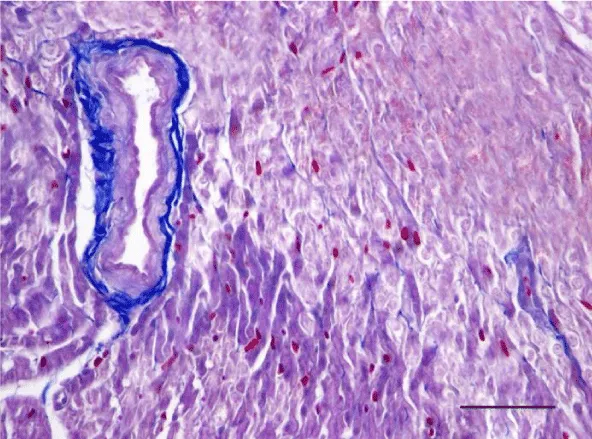

Mallory’s trichrome stain in 2-week-old animals revealed a scarce amount of fine collagen fibers in the walls of the two ventricles. Very few thin and quite short connective tissue fibers were noted in the interstitial space of the left ventricle. More collagen fibers were situated predominantly in the perivascular zone and in the walls of the blood vessels and were stained in an intensive blue color; we noted a slight tendency for collagen fibers to grow from the perivascular zone towards the interstitial space (Figures 3,4).